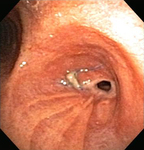

Сужение анастомоза бронха после трансплантации легкого

Из коллекций Хосе Фернандо Сантакруза, дипломированного врача, члена Американской коллегии специалистов в области торакальной медицины, DAABIP, и Эрика Фолка, дипломированного врача, магистра наук; используется с разрешения